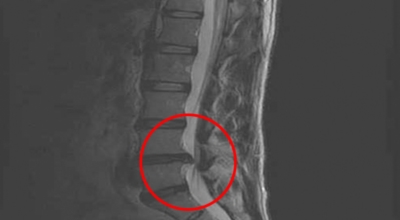

여러 개의 작은 척추뼈가 모여서 척추라는 인체의 기둥을 이루게 되어요. 척추뼈 사이에는 척추뼈끼리 부딪치는 것을 방지하는 쿠션 같은 역할을 하는 '디스크(disc)'라는 말랑말랑한 젤리 같은 구조물이 있는데 우리말로는 '추간판'이라고 하네요.

디스크(추간판)의 한가운데에는 젤리같이 찐득찐득한 '수핵'이라고 하는 성분이 들어 있어요. 그 주변에 수핵을 둘러싸는 '섬유륜'이라 하는 두꺼운 막이 있는데 디스크는 전체적으로 자동차의 타이어와 같은 형태라고 해요. 디스크는 일어선 상태에서는 중력을 받아 납작해져서 바깥쪽으로 약간 볼록한 형태가 된다고 해요.

디스크는 그 특수한 구조 때문에 웬만한 힘이 가해져도 효율적으로 쿠션 역할을 할 수 있겠습니다. 그러나 갑작스럽게 무거운 물건을 들어 올리거나, 부자연스러운 자세를 장시간 취하면 디스크에 무리한 힘이 가해지면서 디스크가 밖으로 돌출이 되게 돼요. 심한 경우 디스크를 감싼 막이 터지면서 그 안에 있는 수핵이 튀어나오게 돼요. 디스크는 대부분이 후방이나 후외방으로 돌출되는데 이 경우에 바로 곁에 있는 신경을 누르게 된다고 해요.

돌출된 디스크는 척추의 어느 부위에나 발생할 수 있답니다. 목에 생기면 '목 디스크', 등에 생기면 '등 디스크', 허리에 생기면 '허리 디스크'라고 부른다고 해요. 이와 같이 디스크가 돌출되어 신경을 눌러 요통 및 다리가 아프고 저린 증상을 일으키는 병을 '추간판 탈출증' 또는 '디스크 탈출증'이라고도 불리워요. 발생 빈도별로 보면 허리 디스크가 가장 흔해요. 그다음이 목 디스크입니다. 등 디스크는 드문 병이라고 하네요.